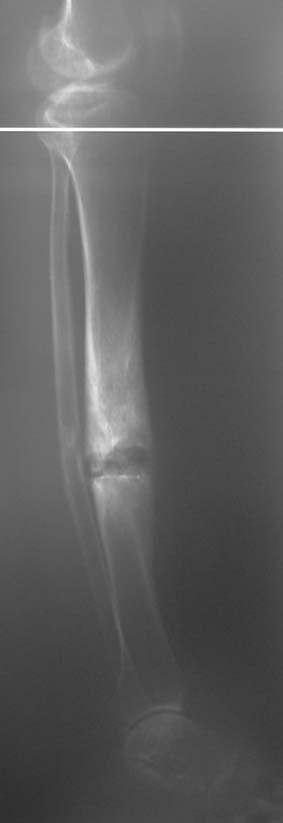

Uygun radikal debridman tüm nekrotik kemik ve yumuşak dokuların çıkartılmasını gerektirir, ve sıklıkla uzuvda instabiliteye neden olur. Kalan kemik ve yumuşak doku defektinin bir şekilde fiksasyonu ve rekonstrüksiyonu gereklidir. İlizarov’un ortaya koyduğu distraksiyon osteogenezi yöntemi, kaynamanın elde edilmesi, deformitenin düzeltilmesi, bacak boy eşitsizliğinin giderilmesi ve segmental defektlerin rekonstrükte edilmesi için başarıyla kullanılmaktadır.

Eksternal fiksatör ile geçen süre (eksternal fiksasyon indeksi), gereken distraksiyon miktarına bağlıdır ve bu süre boyunca bazı komplikasyonlarla karşılaşılabilir. Distraksiyon dönemi sona erdikten sonra, distraksiyon süresinin iki katını aşan konsolidasyon döneminde hastalar eksternal fiksatörü zorlukla tolere edebilirler. Yeterli konsolidasyon sağlanmadan eksternal fiksatör çıkartılırsa ise kırıklar, deformite ve kısalık oluşabilir. Hastanın fiksatör ile birlikte geçirdiği sürenin azaltılması ve böylece hasta konforunun ve aktivite düzeyinin arttırılması için intramedüller çivi üzerinden uzatma yöntemi uygulanmaktadır. Bu yöntemde distraksiyon dönemi sona erdiğinde kemiğin içindeki çivi statik olarak kilitlenmekte ve eksternal fiksatör çıkartılmaktadır. Stabilizasyon intramedüller çivi tarafından sağlandıktan sonra konsolidasyon dönemi gerçekleşmektedir. Bu şekilde hem eksternal fiksatörün uzun süre kalmasından hem de erken çıkartılmasından kaynaklanan komplikasyonların önüne geçilmektedir.